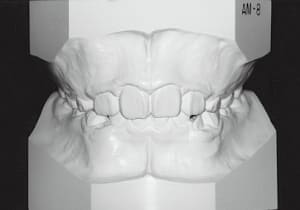

Age at initial visit : 7 y 7 m, male /Protruding upper bite. Open bite. Receding lower jaw. Protruding dual dentition.

The Class II condition is pronounced, with a significant overjet of 12.5 mm(3). Although the teeth size are large, crowding is relatively mild. The maxillofacial structure has good depth and a robust bone framework(5). The mandible itself is solid , robust gonial angle, but there is significant anterior-posterior displacement relative to the maxilla(ANB 10.0°). While there is no confirmed history of thumb-sucking or similar habits, the lower lip is already pushing up against the maxillary incisors. The cause of this condition is unknown.

The first phase of treatment involved extracting the left and right maxillary deciduous canines. The space created was used to forcibly retract the four anterior teeth, thereby aiming to improve lip closure function (6–9, 11). Morphological changes suggest that lip function differed before and after treatment (6, 9). Subsequently, the first premolars erupted, but extraction is planned to secure space for canine eruption (10). A Class II molar relationship remains, but the significant overjet has improved (11).